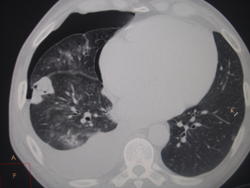

Больной, 42г поступил в терап отделение с диагнозом правосторонний плеврит, жалобы на одышку, резкую слабость. Иногородний, бомж. В июне лечился с пневмонией 10 дней в терапии, с ХИБС, стенокардия, фибрилляция, пневмония рассосалась. после поспупил на 2 дня с плевритом в июле месяце, откачали 1,5 литра, ушел с отделения. Сейчас поступает опять, откачали 3 литра, на слд день направили на СКТ для исключения плеврита онко этиологии. Сегодня хирург говорит, что туберкулез плевры у него. Я за Тб плевры сомеваюсь что то., уж нет отсевов совсем по срезам, при таком объемном поражении, а Вы как считаете коллеги?

Да, ктобы знал, что и лёгкие будут таким нелегкими. Когда очаги по всем полям на разных уровнях- тогда все ясно. Целый час загружала... Потом своих подтвержденных больных загружу, чт было с чем сравнить, пока еще никого не снимала из своих туб больных.

Воздух в правой плевральной полости не смущает Вас??? В поджатом легком, с компрессионной гиповентиляцией, да с ограниченной и свободной жидкостью - огромный простор для поиска ... Коэффициент абсорбции у жидкости какой? Чего они там наоткачивали, цитология будет? Такое рецидивирование не к добру ... Плз - вооон тот крестик на ведите на воооооон тот шарик

По частично коллабированному легкому очаги не оцениваются. Можно насочинять невесть что... Сначала пункция (лаб.диагностика непременно), а потом, при необходимости, КТ-контроль и при уже расправленном легком делать КТ высокого разрешения в зоне интереса и смотреть, что почём. На данный момент свободный гидро(пио?)торакс справа. Деструктивный процесс есть, а какой - однозначно мне не сказать.

Ещё одна мысль: мезотелиома, она тоже копит дотаточно. Жидкость удалишь и она снова появляется. Бомжи от этой болезни не застрахованы.

Подняли июльскую историю болезни, в плевральной жидкости- метастатические клетки. как не увидели? Скорей всего результат приклеили позже, когда больной ушел с отделения. Сейчас в пунктате- оргомное колич эритроцитов. Подтвержается мезотелиома ссиндромом " дойной коровы", когда жидкость копится в большиом количестве.

А что там за круглое "образование" в нижних отделах правого легкого? Я в КТ не соображаю, кто-нибудь знающий подскажите